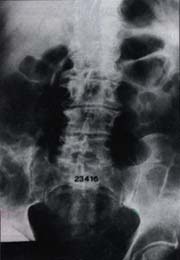

Estas zonas de transición son el resultado a su vez de los cambios morfológicos estáticos y dinámicos, determinados durante el desarrollo filogenético, ontogénico, de actividad y ocupación en la especie humana Figuras 1 y 2.

Fig 1. Espondiloartrosis de la región lumbosacra